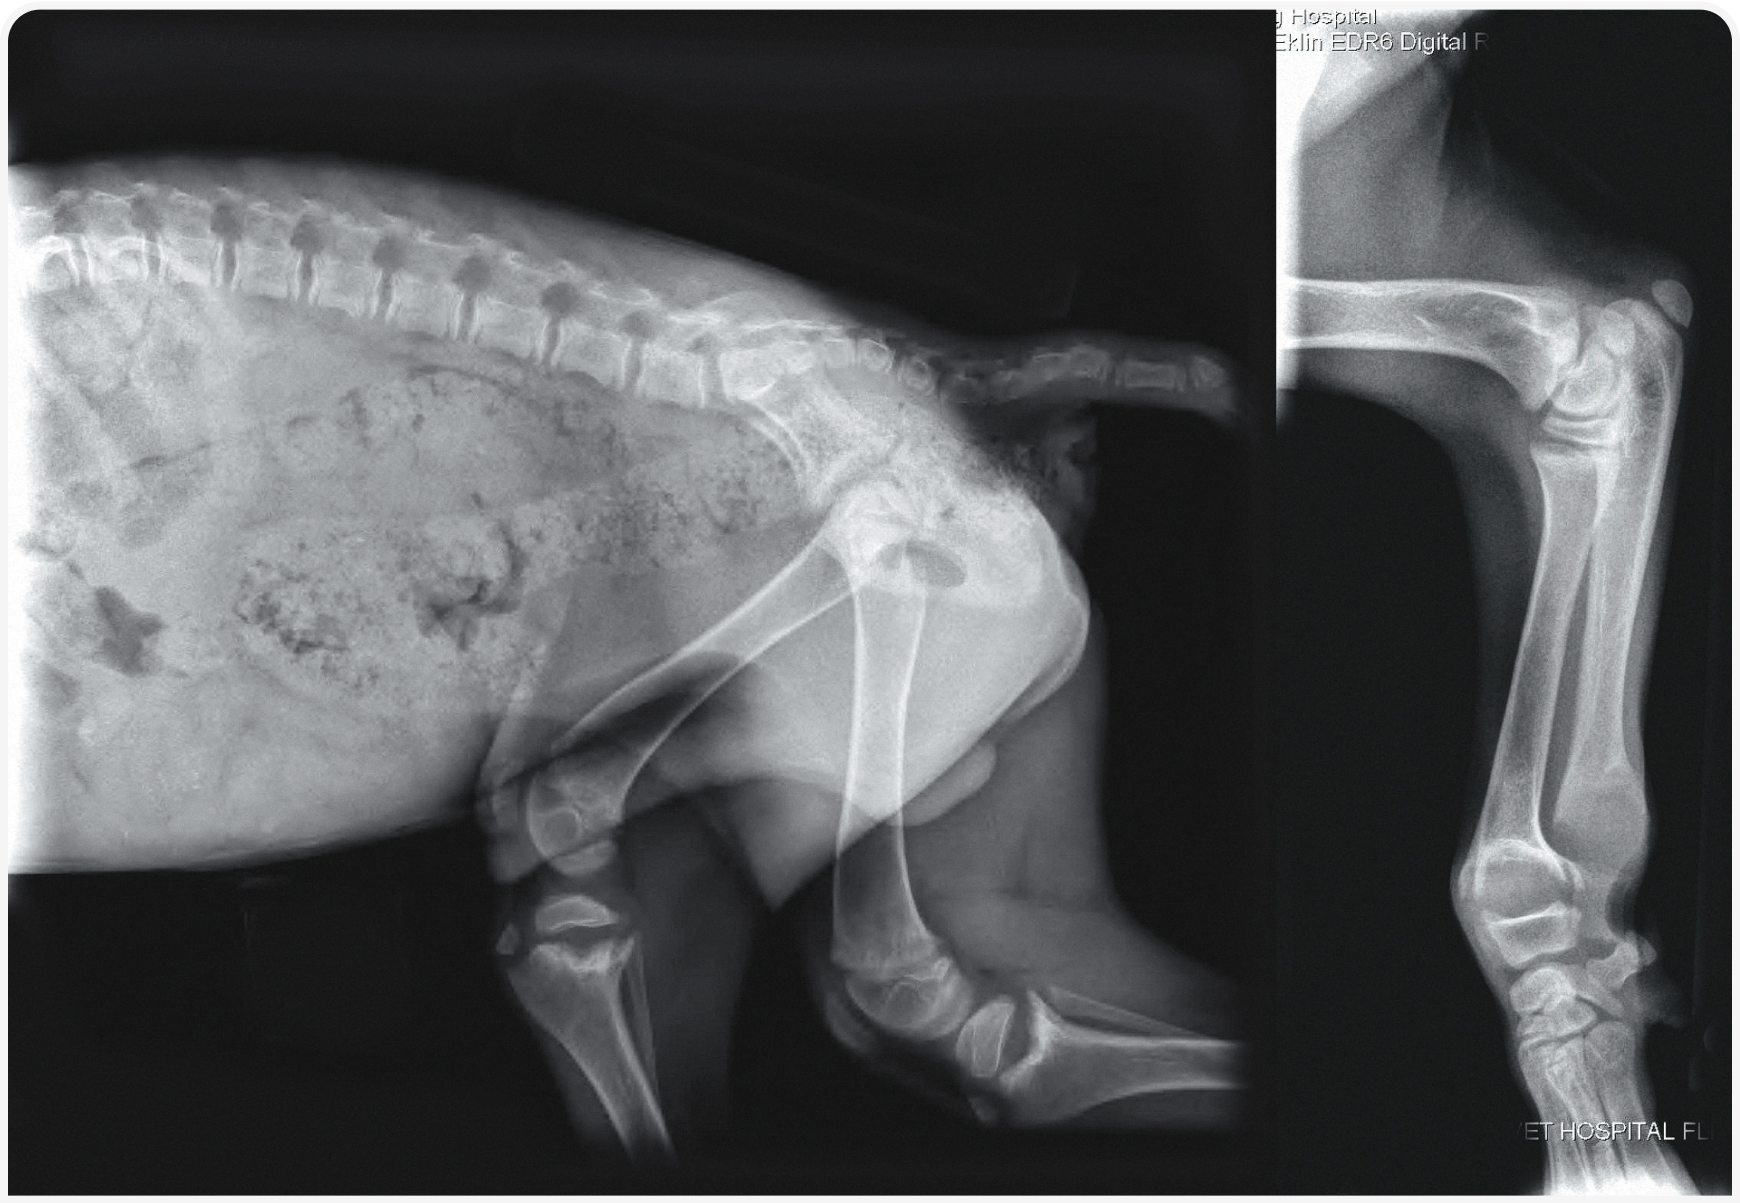

Остеобласты и хондроциты экспрессируют 1α-гидроксилазу и VDR, но неизвестно, является ли участие витамина D в росте и минерализации костей прямым или косвенным. Рахит — это нарушение обмена веществ в костной ткани, обычно развивающееся при дефиците витамина D, кальция или фосфора в рационе или при генетически обусловленных нарушениях их обмена (Рисунок 3). Клинически рахит обычно проявляется расширением метафизарной пластинки роста у быстрорастущих костей, например, лучевой и локтевой. Гистологически, в тканях накапливаются гипертрофированные хондроциты, что приводит к утолщению и искривлению пластинок роста. При несбалансированных рационах с преобладанием мяса без добавки витамина D чаще развивается не рахит, а фиброзная остеодистрофия, вызванная пищевым гиперпаратиреозом. Лечение рахита, вызванного несбалансированным кормлением, состоит в переходе к полноценному и сбалансированному питанию.

Рисунок 3. Рентгенограммы таза в правой боковой проекции и лучевой/локтевой костей молодой (предположительно годовалой) собаки. Пластинки роста лучевой, локтевой и большеберцовой костей значительно расширены и имеют чашеобразную форму, что сопровождается диффузной остеопенией. Эти данные соответствуют диагнозу рахит.